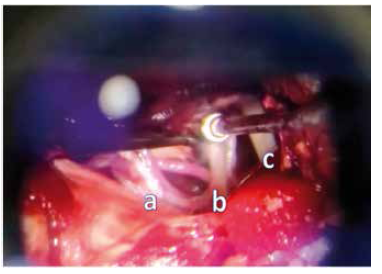

Se planteó procedimiento quirúrgico de descompresión microvascular del nervio trigémino, realizado por abordaje sub occipital lateral izquierdo, encontrándose como principales hallazgos contacto de arteria cerebelosa superior con el nervio trigémino, la misma con trayecto sinuoso y de mayor calibre, además de complejo venoso adherido a su porción dorsal, se realizó micro disección separando ambas estructuras con Gelfoam, liberando de esta forma el conflicto de espacio. (Figura N° 2)

Figura N° 2

Imagen microscópica intraoperatoría evidencia complejos vasculonerviosos del ángulo ponto cerebeloso superior y medio a) Nervio Abducens b) nervio trigémino en contacto con arteria cerebelosa superior además de complejo venoso en su proyección dorsal c) Nervio Facial